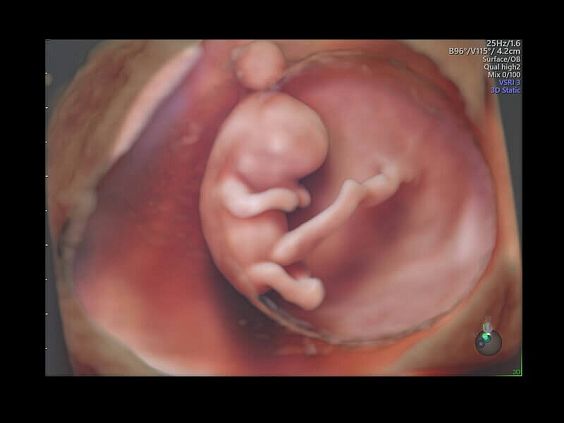

• Программа объемной визуализации плода классический HD-Live + расширенный пакет Hdlive Silhouette и Studio:

• HDlive Silhouette - режим "Силуэт" с подчеркиванием границ тканей и объектов, "объем в объеме"

Инновационная технология визуализации HDlive обеспечивает получение реалистических изображений за счет эффекта объемного зрения, повышая достоверность клинической оценки. Теперь режим HDlive дополняют две новые функции:

• Технология HDlive Silhouette — задает разный уровень прозрачности, помогая выявлять контуры внутренних структур и точнее оценивать состояние плода в первом триместре.